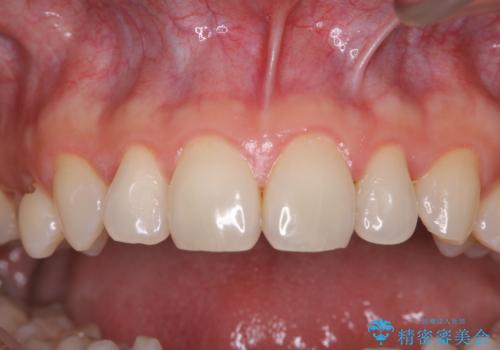

終了時

40年ぶりの来院との事で全体的に、古くからの歯垢・歯石が硬く多く付着していたため、自費クリーニング(PMTC)60分1万円+TAXコースを行いました。

よって、歯科衛生士による専門的なクリーニングを定期的に行うことがとても大切です。